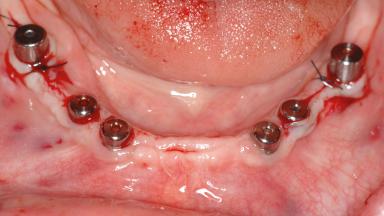

Le Fort I Interpositional Graft and Mandibular Sandwich Osteotomy for Maxillofacial Rehabilitation after Severe Periodontitis

A 47-year-old woman who had suffered from aggressive periodontitis requiring a number of periodontal interventions over more than 10 years was referred by her general dental practitioner and periodontologist for bone augmentation and implant therapy. Her failing dentition had already been scheduled for extraction. The patient expressed a desire for implant-supported fixed restorations and esthetic improvement of her lower face. She had agreed to consult with a maxillofacial surgeon after the referring dentist had suggested bone augmentation. An initial examination by the maxillofacial surgeon revealed mobility of all residual teeth in a patient who was very unhappy with the function of her removable partial dentures. Due to periodontally migrated flaring teeth and loss of occlusal support, the vertical dimension of occlusion was dramatically reduced. The patient was displeased with her lower face because of deepened nasolabial, commissural, and supramental folds.

# of Implants 14

Bone Augmentation Horizontal|Sinus Floor Elevation|Staged|Vertical